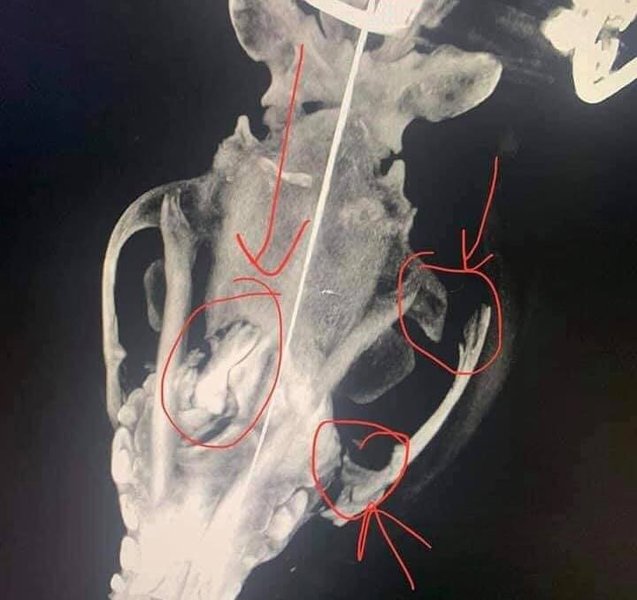

Кличка пса "Марс". | Фото: facebook / OA Iva

Состояние собаки крайне тяжелое, у нее раздроблена челюсть, множественные переломы костей, и проблемы со зрением. Врачи ввели собаку в искусственную кому. Прогнозы неутешительные. На реабилитацию собаки может уйти от 6 месяцев до двух лет.